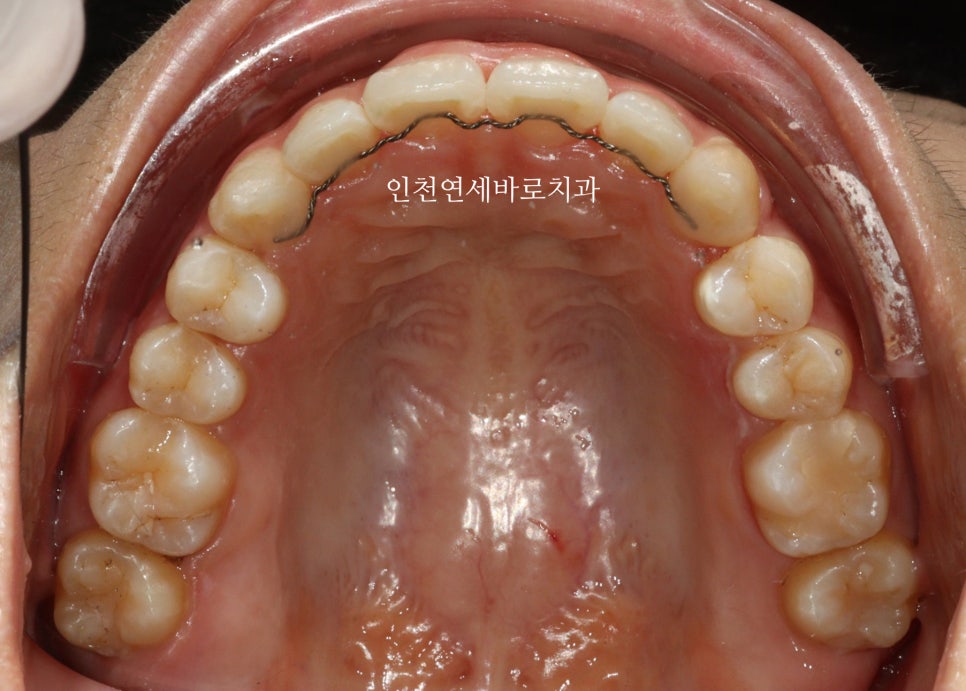

시작 후 약 4-5달 후 사진입니다.

인비절라인은 투명교정장치만 착용하는 경우가 대부분이긴합니다.

하지만 이 환자분 처럼 고무줄을 동반해야하는 경우도 있습니다.

위 사진이 7월에 재제작 했을 때 모습입니다.